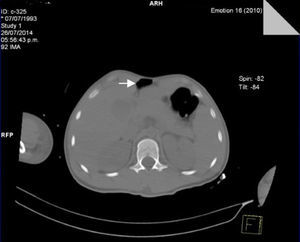

A las 72 h de su ingreso, presentó enfisema subcutáneo en tórax anterior que se extendió a cuello, por lo que se le realizó Tc simple de tórax y de abdomen, con el hallazgo de neumomediastino, contusiones pulmonares bilaterales y neumoperitoneo (figs. 2 y 3). Continuando con apoyo mecánico ventilatorio. Se descartó lesión esofágica por esofagograma con medio hidrosoluble, al igual que lesión traqueobronquial por broncoscopia flexible; además, no se identificaron datos de irritación peritoneal, por lo que se establece como causa de neumomediastino y neumoperitoneo el efecto Macklin.

En los casos en que la radiografía de tórax es normal (menos del 10%), el estudio de elección es la Tc, que es considerado el «estándar de oro», aun en pacientes con hallazgos radiográficos sugestivos1,10. El efecto Macklin aparece como una colección lineal de aire contigua a la vaina broncovascular y los hallazgos característicos de enfisema intersticial por efecto Macklin, se presentan como una tríada de: 1) enfisema intersticial, 2) a bronquio, y 3) a vaso sanguíneo pulmonar3,16. La Tc respecto al neumomediastino y al neumoperitoneo tiene una alta sensibilidad (> 95%) y especificidad (> 85%) para descartar lesión mayor de tracto aerodigestivo; sin embargo, siempre se debe descartar la posibilidad de lesión esofágica o traqueal con otros métodos diagnósticos10.

La presencia de neumoperitoneo generalmente está asociada a la perforación de víscera hueca y, por lo tanto, requiere manejo quirúrgico urgente; en 5-15% de los casos, no es resultado de perforación visceral, y se relaciona la mayoría del tiempo con intervenciones médicas17. Mularski et al.17 identificaron 2 grupos como causas no quirúrgicas de neumoperitoneo: 1) causa abdominal (aire postoperatorio, diálisis peritoneal, procedimientos endoscópicos gastrointestinales, y 2) causa torácica (ventilación mecánica, resucitación cardiopulmonar, lesiones pulmonares por trauma, neumotórax) que señalan que cuando el dolor y la distensión abdominal son mínimas, y los signos peritoneales, fiebre y leucocitosis están ausentes, las causas no quirúrgicas deben considerarse17,18.